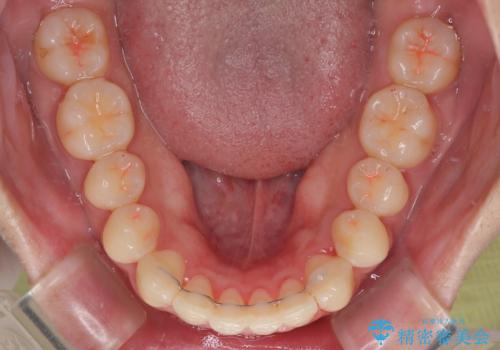

- 今回は「下の前歯のデコボコを治したい」と来院された患者様の症例をご紹介します。

診察してみると、下の前歯が並ぶためのスペースが足りないことが、歯並びがデコボコしている原因でした。

下の前歯の歯と歯の間をわずかに削ってスペースを作る(IPR)

奥歯を後ろに動かして、前歯が並ぶためのスペースを確保する

この計画により、デコボコだった下の前歯はしっかりと並び、わずか1年で治療を終えることができました